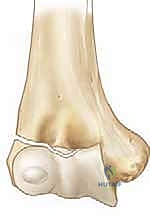

* تصنيف جاكوب (Jakob Classification): وهو الأهم في تحديد العلاج:

* الدرجة الأولى (Stage 1): الكسر غير متحرك من مكانه (أقل من 2 ملم)، والمفصل سليم.

* الدرجة الثانية (Stage 2): الكسر متحرك (أكثر من 2 ملم) ولكن الجزء المكسور لم يدر حول نفسه.

* الدرجة الثالثة (Stage 3): الكسر متحرك بالكامل، والقطعة المكسورة دارت حول نفسها بسبب شد العضلات، مما أدى لانخلاع جزئي في المفصل.